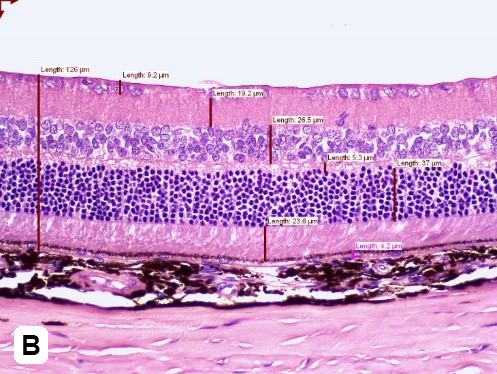

Figure 3: Quantitative image analyses of retinal layers using H&E staining of STZ-induced (A) vs non-induced (B) retina at Day 72 post-induction. An increase in the total thickness of retinal and ONL is found in STZ-induced animals. Magnification 200x)